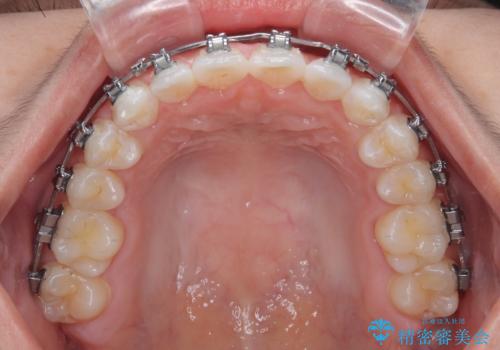

- 矯正装置

- メタルブラケット

- 7ヶ月

- 上下前歯のデコボコを気にして来院された患者様です。

ワイヤー矯正でもマウスピース矯正でも可能でしたが、短期間で、自身の手を煩わせることなく治療を行いたいとのことで、ワイヤー装置にて矯正治療を行うこととしました。